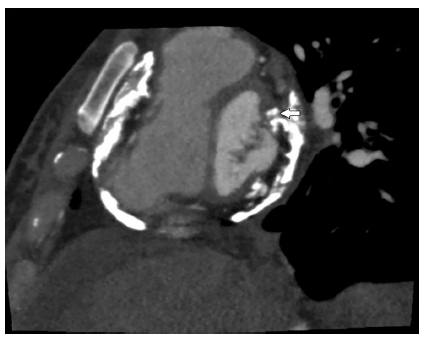

La angiotomografía cardiaca reportó calcificación pericárdica circunferencial difusa con calcificaciones en la pared miocárdica del ventrículo izquierdo, incluyendo el músculo anteromedial papilar de la válvula mitral. El estudio de las arterias coronarias fue normal y el score de calcio fue de cero (figs. 2 y 3).

Figura 2 Tomografía computarizada de tórax con calcificación pericárdica difusa y compromiso de la válvula mitral.